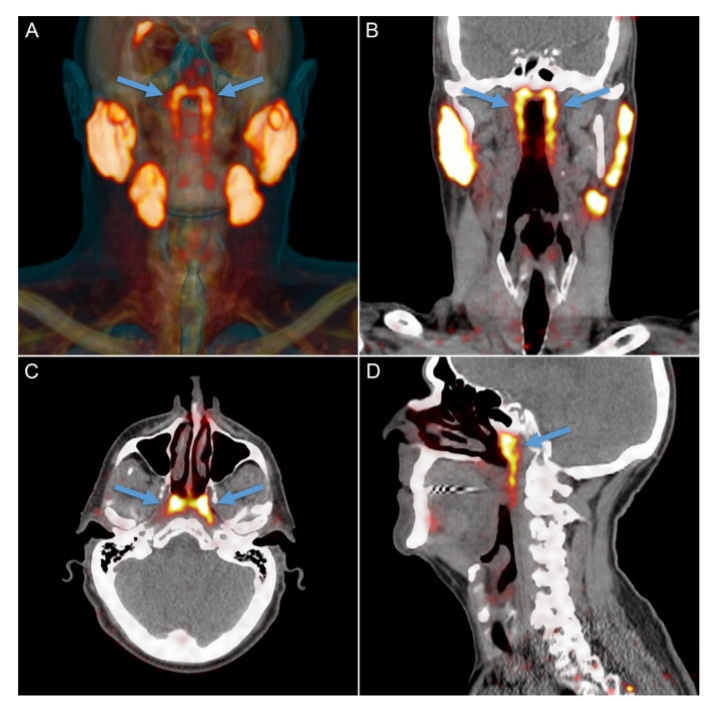

除了以上五种公认的进化理论外,最近,荷兰癌症研究所(NKI)的放射肿瘤学家Wouter Vogel意外发现了一组秘密的新器官:藏在人体喉咙深处上部的唾液腺,隆凸唾液腺。这个发现可能会对癌症的治疗产生重要影响。

在以往的医学记载中,人类只有三个明显的唾液腺——舌下腺、颌下腺和腮腺,分别位于舌头下方、下颌下方和脸颊后部的下颌背面。除此之外,咽喉和口腔粘膜组织中或许也散布着上千个极小的唾液腺。它们分泌唾液,帮助我们咀嚼、吞咽和消化食物,并保持我们的口腔湿润及牙齿健康。而这次新发现的隆凸唾液腺位于鼻子后面一块被称为咽鼓管隆凸的软骨上,平均长度约1.5英寸(即3.9厘米)。

Wouter Vogel是在探查头部、颈部或脑部癌症放疗后的唾液腺损伤(导致消化、语言和口腔感染增加等问题)时,发现这组从未被描述和记录过的颈部唾液腺的。为了证实人体的隆凸唾液腺这一最新发现的非偶然性。Vogel及其同事对100名患者进行了扫描(由于研究者是聚焦前列腺癌,所以其中99位患者为男性),还解剖了两具尸体,最终发现所有人都拥有这一“新的”腺体。这一惊喜发现于10月16日正式发布在《放射治疗与肿瘤学》(Radiotherapy & Oncology)上。

新器官的发现,可以帮助医生在使用放射性治疗法治疗癌症的时候,设法避免在患者的头部和脖子部位,对唾液腺进行照射。因为在使用放射性疗法对头部、颈部进行治疗时,我们可以避免照射到这些唾液腺而导致这些唾液腺受到影响。